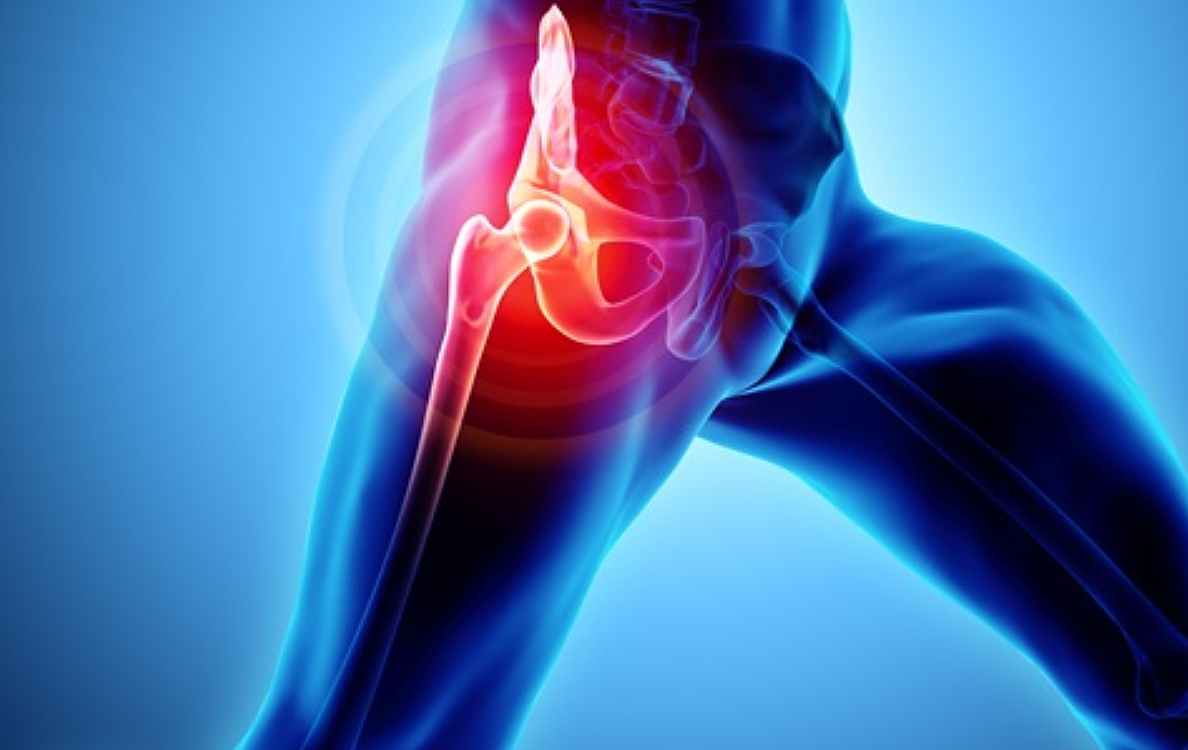

우리나라에서 발생하는 고관절 통증 증상의 가장 큰비중(70%)을 차지하는 대퇴골두 무혈성 괴사는특히 30~50대 젊은 남성에서 많이 발생하는 것으로 알려져 있습니다. 이 질환은 고관절의 기능을 완전히 잃게 할수 있어 주의가 필요합니다.

고관절은 골반 뼈 속에 공처럼 생긴 대퇴골의 골두가 맞물린 관절입니다. 대퇴골두는 다른 부위에 비해 혈액 순환 장애가 쉽게 올 수 있으며, 혈액 순환 장애는 대퇴골두 무혈성 괴사를 유발합니다. 뼈가 썩으면 몸의 하중을 정상적으로 견디지 못해 미세구조에 골절이 생기고, 심각한 통증이 발생합니다.

뚜렷한 원인은 밝혀지지 않았지만, 과다한 음주가 골 괴사의 위험을 높이는 가장 큰 원인입니다. 형외과 전문의는 “대퇴골두 무혈성 괴사는 여성보다는 남성에게서 많이 나타나고 환자의 60%는 양쪽 고관절 통증 증상에 모두 나타난다”며 “발병 요인 중 한국 남성들의 음주 습관이 큰 원인으로 꼽히고 있습니다. 자주 술을 마시게 되면 혈액에 콜레스테롤과 지방 등이 쌓이게 되고 이것이 혈관을 수축시키는데, 이때 혈압이 증가하고 혈액이 응고되면서 혈액 순환을 방해하게 됩니다. 과음으로 인해 급성으로 진행돼 고관절 뼈가 주저 앉는 사례도 있어 조기에 치료받는 것이 중요합니다.